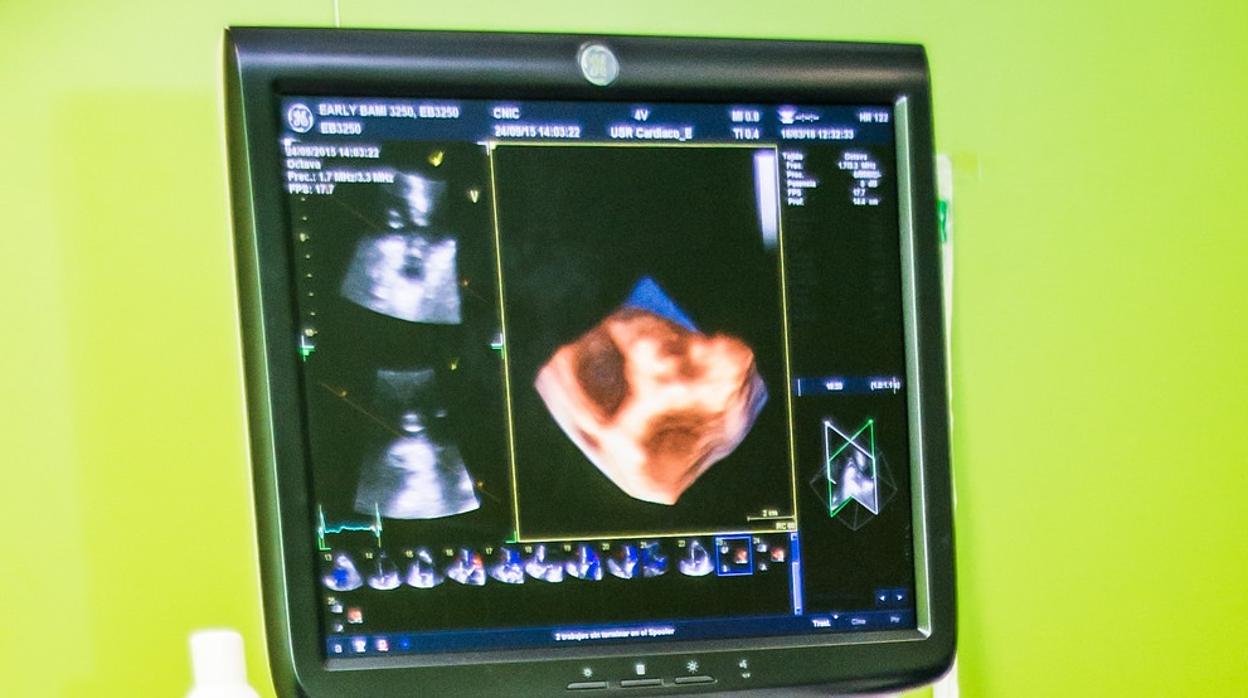

Este es el impacto de Covid-19 en el corazón

Los ecocardiogramas identifican diferentes tipos de daño en la estructura del corazón que experimentan los pacientes con covid-19 después de una lesión cardíaca. Dichas anomalías están asociadas con un mayor riesgo de muerte.

Los ecocardiogramas , también denominados ultrasonidos cardíacos, muestran los devastadores efectos del covid-19 en el corazón de los pacientes. Lo han visto investigadores de la Escuela de Medicina Icahn del Hospital Mount Sinai de Nueva York (EE.UU.) en un estudio que ... se publica hoy The Journal of the American College of Cardiology (JACC), que identifica diferentes tipos de daño en la estructura del corazón que experimentan los pacientes con covid-19 después de una lesión cardíaca que pueden estar asociados con enfermedades mortales que incluyen un infarto, embolia pulmonar, insuficiencia cardíaca y miocarditis. Dichas anomalías están asociadas con un mayor riesgo de muerte entre los pacientes hospitalizados.

«Este es uno de los primeros estudios que proporciona datos ecocardiográficos y electrocardiográficos detallados en pacientes hospitalizados con covid-19 y evidencia de laboratorio de lesión miocárdica», explica el investigador Gennaro Giustino . «Hemos visto que en los pacientes con covid-19 que se sometieron a un ecocardiografía transtorácica había distintas anomalías estructurales cardíacas que estaban presentes en casi dos tercios de los pacientes».